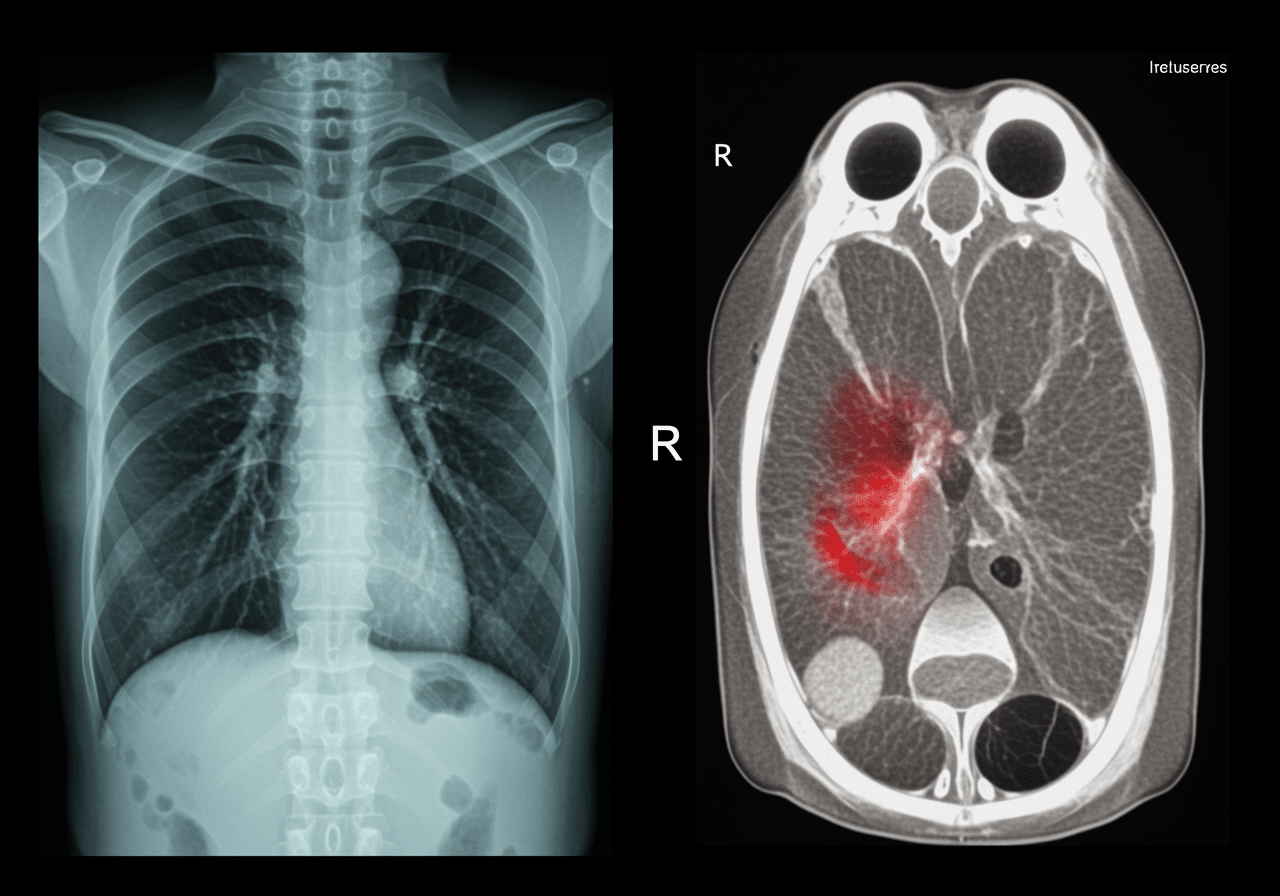

Can chest X-ray detect pulmonary embolism?

No, chest X-ray cannot directly visualize pulmonary embolism as blood clots are not visible on plain radiographs. However, chest X-ray helps exclude alternative diagnoses (pneumonia, pneumothorax, heart failure) and may show indirect PE signs (Westermark sign, Hampton's hump) suggesting diagnosis. Priority ER uses chest X-ray as initial screening identifying pneumonia or pneumothorax, then performs CT pulmonary angiogram when PE clinically suspected based on Wells criteria, D-dimer elevation, or PERC rule assessment. CT angiography remains gold standard for PE diagnosis providing definitive visualization of clot location and burden.

How do doctors differentiate pneumonia, pneumothorax, and PE?

Clinical presentation differs significantly: pneumonia presents with fever, productive cough, and localized infiltrate on chest X-ray; pneumothorax shows sudden pleuritic chest pain, decreased breath sounds, and visible lung collapse on imaging; PE causes sudden breathlessness without fever, leg swelling, and filling defects on CT angiogram. Priority ER emergency physicians perform comprehensive evaluation including vital signs (fever suggests pneumonia, tachycardia with normal oxygen suggests PE), physical examination (decreased breath sounds indicate pneumothorax), and appropriate imaging (chest X-ray first-line, CT angiogram for suspected PE) distinguishing these conditions requiring different treatments.